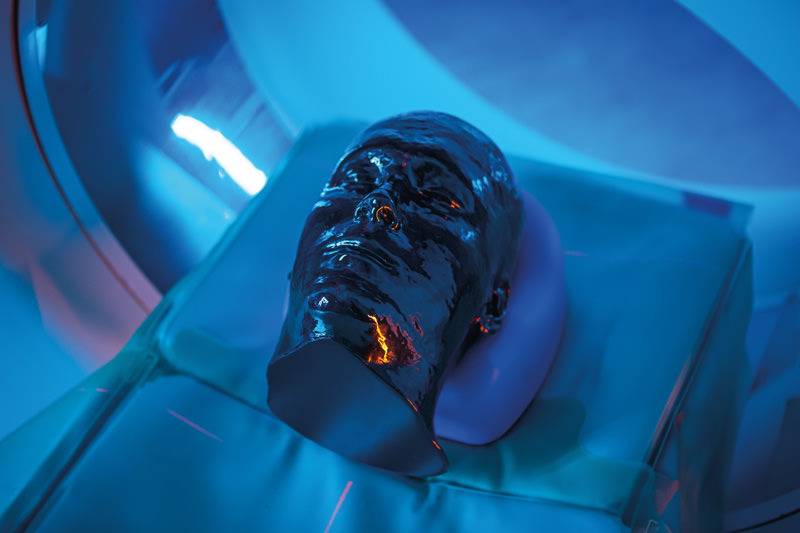

Dieses Phantom ist aus echten Patientendaten erstellt und wird mit neuester Technologie hergestellt. Knochen, Gefäße und Weichteilgewebe werden authentisch dargestellt mit realistischen CT-Werten für alle Gewebe bei 120 kVp Röhrenspannung in der CT. Wenn das Phantom vorwiegend bei anderen Röhrenspannungen (z. B. 100 kVp) eingesetzt werden soll, kann die Kalibrierung der CTWerte auf Wunsch entsprechend angepasst werden. Das Phantom liefert realistische Gewebekontraste in der Röntgen-Bildgebung. Lufträume sind durch ein Material mit etwa -80 Hounsfieldeinheiten aufgefüllt.

Das Kopf - Phantom liefert eine äußerst realistische Simulation einer Kopf- und Hals-CT-Angiographie (mit arterieller Kontrastierung) eines Patienten mit einer arteriovenösen Malformation auf der rechten Seite. Das Phantom wird in originalgetreuem Maßstab geliefert und beinhaltet die Halswirbelsäule bis zur Grundplatte des fünften Halswirbels.

Größe: 19x23x27cm